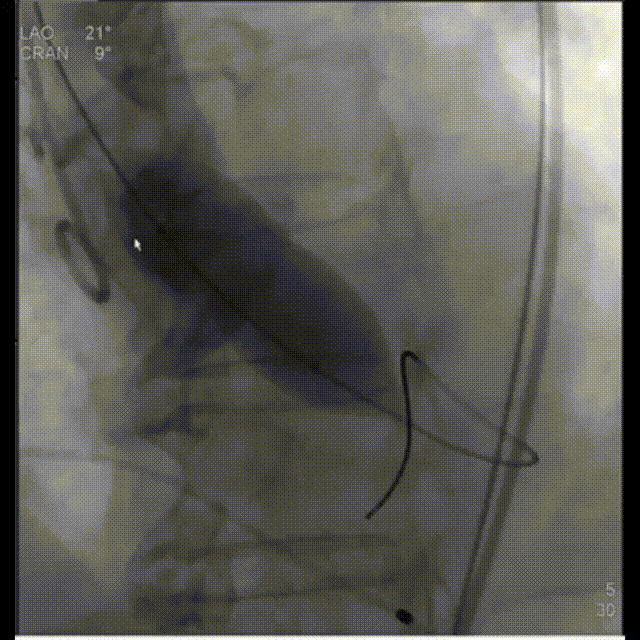

3.根据术前CT评估,球囊预扩角度为LAO 21° CRA 9°(左冠切线位)充分评估冠脉灌注情况,释放角度为RAO 10° CAU 28°(右足位)。使用18mm球囊预扩,根据沛嘉TaurusElite®产品设计特点采取瓣环平面下0-2mm高度释放策略。

主动脉根部造影

球囊预扩